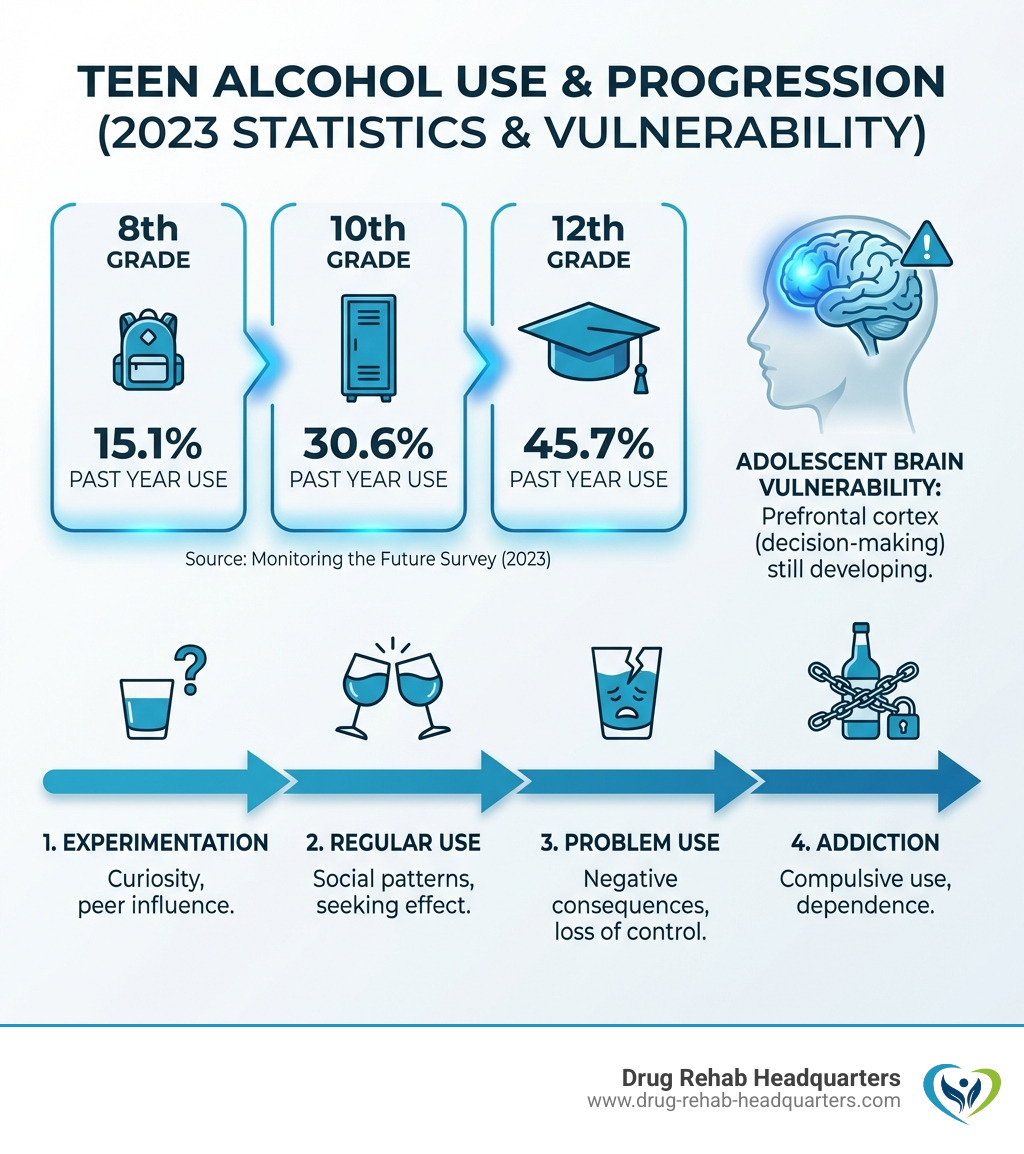

The statistics paint a concerning picture. According to the Monitoring the Future survey, 45.7% of 12th graders reported past-year alcohol use in 2023. Even more troubling, the CDC reports that the greatest percentage increase in drug overdose deaths from 2019 to 2020—a staggering 49%—occurred among young people aged 15-24.

The Impact of Alcohol on the Developing Teen Brain

The adolescent brain is still developing, especially the prefrontal cortex, which controls decision-making and impulse control. Introducing alcohol during this critical period can have lasting consequences.

When alcohol enters this delicate system, it interferes with normal brain development, which can lead to:

- Impaired Decision-Making: Alcohol further impairs a teen’s underdeveloped ability to weigh consequences, increasing risky behaviors.

- Increased Impulsivity: Alcohol worsens natural teen impulsivity, leading to poor choices with serious repercussions.

- Higher Risk of Addiction: Early alcohol use can rewire the sensitive adolescent brain, increasing the risk of lifelong addiction.

- Long-Term Cognitive Issues: Chronic use can impair memory, learning, and academic performance, causing long-term cognitive deficits.

- Mental Health Vulnerability: Alcohol can worsen or trigger mental health conditions, leading to a complex dual diagnosis.

This vulnerability highlights the need for early intervention and specialized alcohol rehab for teens. Addressing alcohol use early protects a teen’s brain and future. Learn more in our resource on Adolescent Substance Abuse Health Risks.